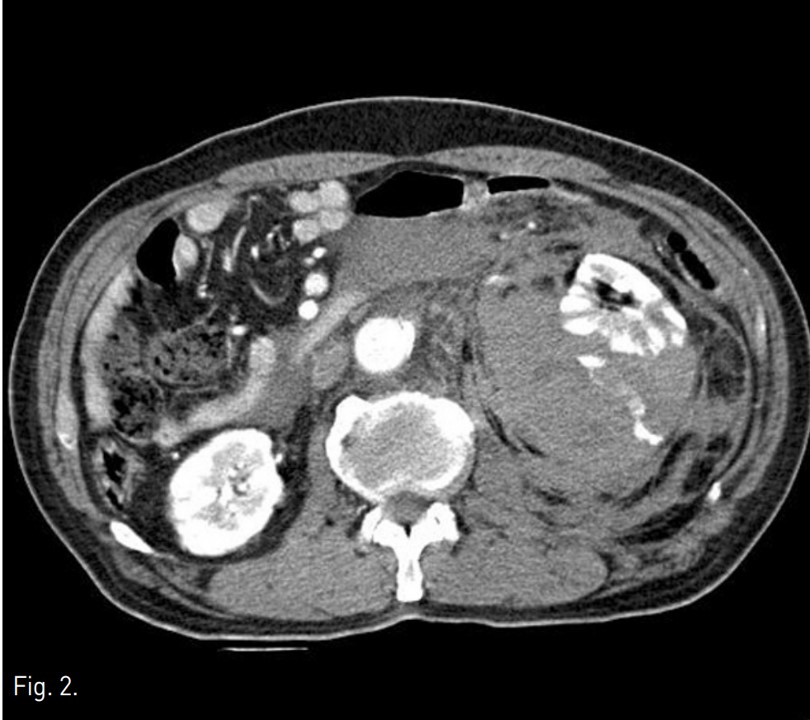

ESWL 시술 전 촬영한 KUB상 좌측 콩팥의 하극 부위의 콩팥돌로 보이는 고음영이 있음(Fig. 1). ESWL 시술 후에 발생한 통증으로 시행한 전산화단층촬영(CT)에서 좌측 콩팥주위 공간에 큰 혈종이 있으며 이로 인해 콩팥이 앞쪽으로 밀렸으며, 출혈로 보이는 조영제 누출이 있음(Fig. 2).

Fig. 1.

Fig. 1. KUB obtained before ESWL shows high density suggesting renal stones in lower pole of the left kidney